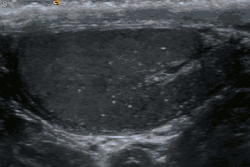

Esta doença geralmente é descoberta incidentalmente durante a ultrassonografia do escroto. Pode ser encontrada em indivíduos normais ou em associação a uma grande variedade patologias testiculares benignas e malignas, principalmente dos tumores testiculares.[1]

Estudos científicos não comprovam se a microlitíase pode ser considerada a causa de outras patologias. Entretanto, há evidências que justificam o acompanhamento ultrassonográfico dos pacientes portadores de microlitíase com a finalidade de diagnosticar precocemente os tumores testiculares.